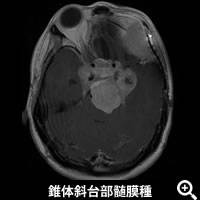

頭蓋底髄膜腫

頭蓋底という脳を支えている頭蓋骨底面の深い場所に発生する髄膜腫の手術を数多く行っています。当院では頭蓋底手術(頭蓋底手術へリンク)を脳神経外科・頭頸部外科(耳鼻咽喉科)・形成外科のエキスパートにより構成される頭蓋底外科チームを組んでおり、必要時はこの3科合同チームで手術を行います。これにより、いろいろな方向から腫瘍を安全に摘出し、複雑な再建も可能となっています。